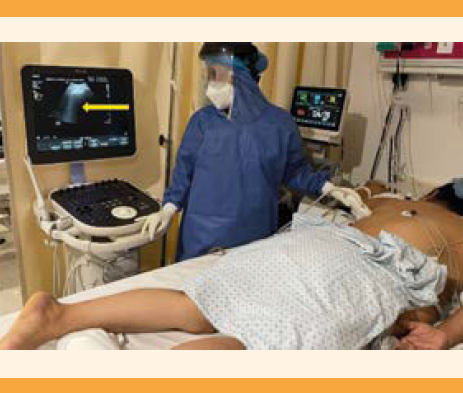

El ultrasonido pulmonar es un método diagnóstico para detectar afecciones pulmonares y pleurales periféricas con alta precisión (sensibilidad mayor de 90% y especificidad del 95%).54,55,56.Esta herramienta ha demostrado su influencia en el tratamiento de pacientes asintomáticas en quienes la tomografía no se consideró de inicio; en quienes tienen síntomas leves que no otorgan su consentimiento para una tomografía; en pacientes asintomáticas con tomografía inicial no patológica y en el seguimiento de la respuesta al tratamiento en pacientes sintomáticas.57 El ultrasonido pulmonar se sugiere como un método confiable, disponible en muchas instalaciones y preciso para la evaluación inicial. El ultrasonido pulmonar puede mostrar signos específicos de neumonía intersticial. Se requiere un transductor lineal o convexo, de preferencia. El ultrasonido pulmonar suele practicarse en posición sentada, lateral o supina. El hemitórax se divide en seis regiones, con la ayuda de líneas axilares anteriores y posteriores: 2 anteriores, 2 laterales y 2 posteriores por cada hemitórax; cada región se examina con cortes sagital y axial.58 Figuras 3 y 4

Figura 3 Ultrasonido pulmonar. Procedimiento para el ultrasonido pulmonar en paciente en puerperio quirúrgico con estrategia ventilatoria en decúbito prono por COVID-19. Cuidados Críticos Obstétricos en área COVID-19 del Hospital General Dr. Miguel Silva, Morelia, Michoacán, México. En la flecha señalan las líneas B (artefactos subpleurales). Cortesía: Dr. Luis Alberto Ruiz Marines.

Figura 4 Ultrasonido pulmonar. Procedimiento para el ultrasonido pulmonar en paciente en puerperio quirúrgico con estrategia ventilatoria en decúbito prono por COVID-19. Cuidados Críticos Obstétricos en área COVID-19 del Hospital IMIEM Estado de México. Cortesía Dr. Christian Alberto Herrera Venegas.

La paciente grave deberá recibir atención intrahospitalaria en un área obstétrica designada y adecuada para la atención de pacientes COVID, de preferencia en un cuarto aislado con presión negativa, con equipo de procedimientos para parto y atención neonatal. La paciente debe ser atendida por personal de salud con equipo de protección personal completo. Lo ideal es tomar una prueba PCR para influenza y SARS-CoV-2 y evaluar la severidad del cuadro mediante la rápida cuantificación de la insuficiencia orgánica secuencial, conocida por sus siglas en inglés como qSOFA. (Cuadro 6) Un puntaje mayor o igual a 2 identifica a la paciente que amerita atención intrahospitalaria en un área de cuidados intensivos.68 La paciente apta para recibir atención en cuidados intensivos deberá ser valorada oportunamente por un equipo multidisciplinario, obtener cultivos para estreptococo del grupo B, valorar la anticoagulación y el beneficio del esteroide o terapia anti IL-6 (según corresponda). Además, contar con un ultrasonido que corrobore la frecuencia cardiaca fetal, la presentación del feto, el peso estimado de éste y la cantidad máxima de líquido amniótico y localización de la placenta.69

Es importante la vigilancia del bienestar de la madre y el feto. La vigilancia del feto en pacientes hospitalizadas se efectúa con monitoreo electrónico durante 20 minutos en búsqueda de datos ominosos cuando se considera al feto como viable en el centro hospitalario de atención.